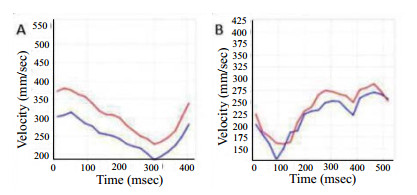

目前的理论认为CSF的脉动压力是由脉络丛扩张力所驱动的。自二十世纪80年代以来,国外开始运用各种MRI技术对CSF进行生理病理研究,Feinberg等[14]和Bergstrand等[24]率先将研究血管系统的MRl速度成像用于CSF动力学研究,发现中脑导水管的CSF流动信号强度的变化与心动周期有关。在二十世纪90年代,Enzmann等[25]将PC cine MRI用于测量脑血管中的平均血流量。PC cine MRI是由相位相反的两极组成的流动梯度磁场,通过对流动的液体进行两次不同的流动编码,经机器自带的工作站产生两组图像即相位幅度图像和相位对比流动图像[26]。由于磁共振扫描技术不断地发展,PC cine MRI已经成为目前观察CSF流动的非侵袭性技术[27],能够无创、准确以及定性、定量测量CSF的流速,无需加入对比剂,且对缓慢的流动敏感等特点。大多数国内外学者将PC cine MRI用于人体CSF动力学研究[28-29],却很少见将该序列用于研究动物的CSF动力学,尤其在颅内高压致脑疝之后再进行CSF动力学的研究鲜有报道。在本研究中,注血前广西巴马小型猪的CSF峰值流速绝对值居于正常水平,在注血完成后,由于颅内压持续增高造成脑组织移位形成脑疝,导致桥脑前池消失,造成CSF循环通道梗阻,CSF峰值流速绝对值降低,CSF流动呈现出低动力学改变。根据Monro-Kellie学说[30],由于脑、脑脊液和颅内血液的总量是不变的,当其中一个增加会导致其余两个中的一个或两个减少。该学说可以用来解释当达到颅内高压形成脑疝以后,CSF峰值流速绝对值降低,颅内CSF容量减少。本研究还发现,在注血前CSF的流速波形近似于正弦、余弦波形,波形较为平滑,在形成脑疝以后CSF的流速波形出现紊乱、畸形(图 2)。形成脑疝后,MAP较前升高,但是颈动脉峰值流速绝对值的前后改变差异无统计学意义,可能与脑部供血的自动调节功能有关,在代偿期防止脑缺血的发生。

| 注射自体动脉血前脑脊液流速的波形近似于正弦、余弦波形,注射自体动脉血后脑脊液流速波形出现紊乱、畸形; A:注射自体动脉血前正常CSF峰值流速绝对值是380 mm/s;B:注射自体动脉血后形成脑疝后CSF峰值流速绝对值是289 mm/s 图 2 CSF流速图 Fig 2 CSF flow chart |

|